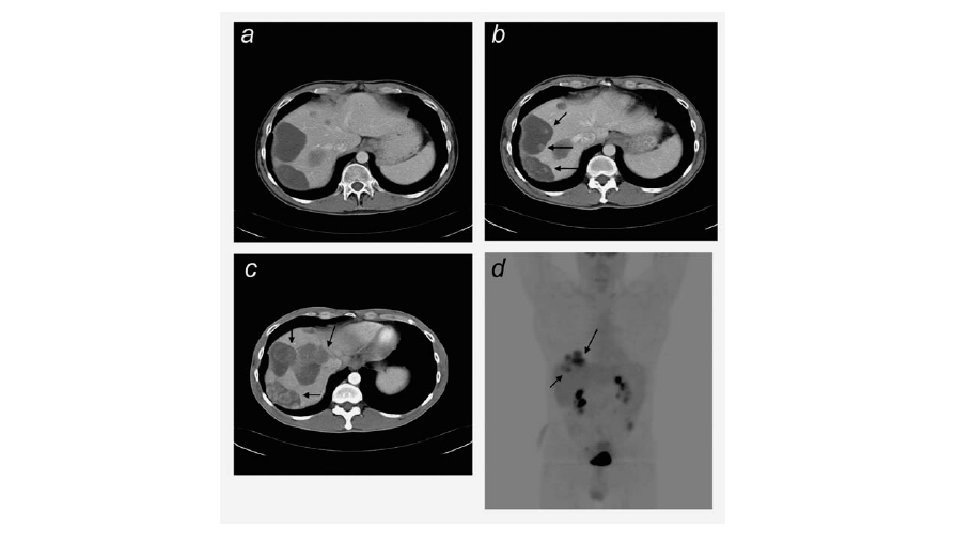

PSEUDO PROGRESSION • Increase in size • Liver metastasis May happen even in responsive tumors

a. PET b. CHOI c. RECIST

CHOI CRITERIA Minimum 10% decrease in tumor size Minimum 15% decrease in tumour density